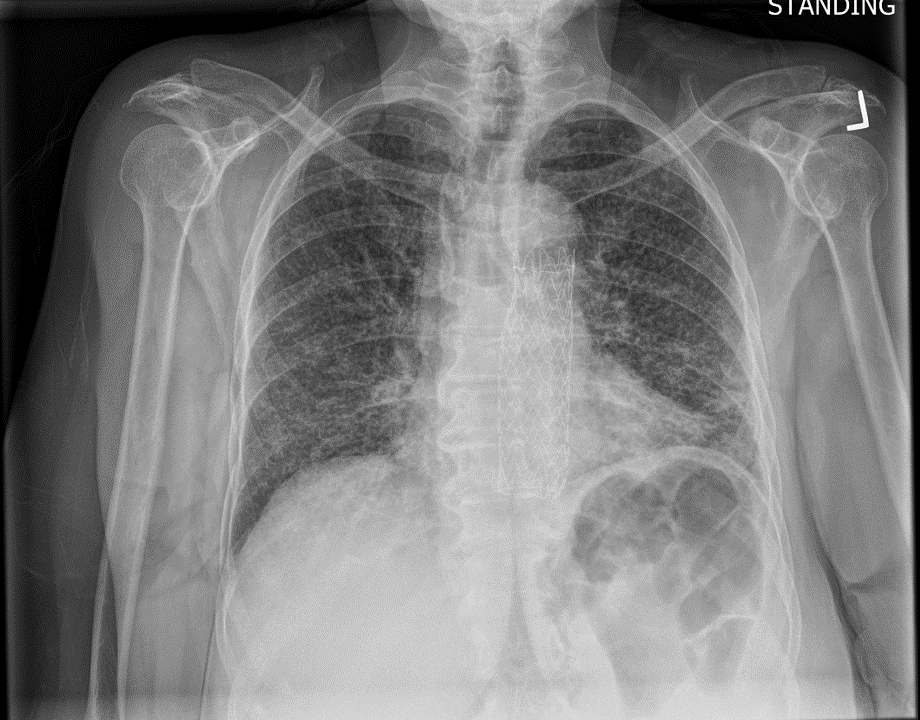

Today we discussed a case of a young man with otherwise no medical history presenting with subacute dry cough, malaise, and weight loss. On exam he was septic on presentation with notable oral thrush. CXR revealed bilateral interstitial infiltrates and a RUL cavity with air fluid level which was confirmed on CT. LDH was elevated. He was confirmed HIV positive with a low CD4 count in the single digits, and BAL confirmed the diagnosis of PCP/PJP pneumonia!

• CXR: Classic description is bilateral interstitial infiltrates

• Rare instances: Lobar infiltration, nodules, cavitary lesions, pneumothorax